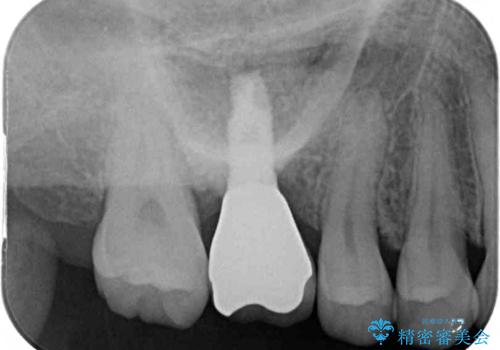

その後は、オールセラミッククラウンにて補綴することとしました。

仮歯装着中に頻繁に脱離したため、オールセラミッククラウンは脱離の少ないスクリュータイプとしました。